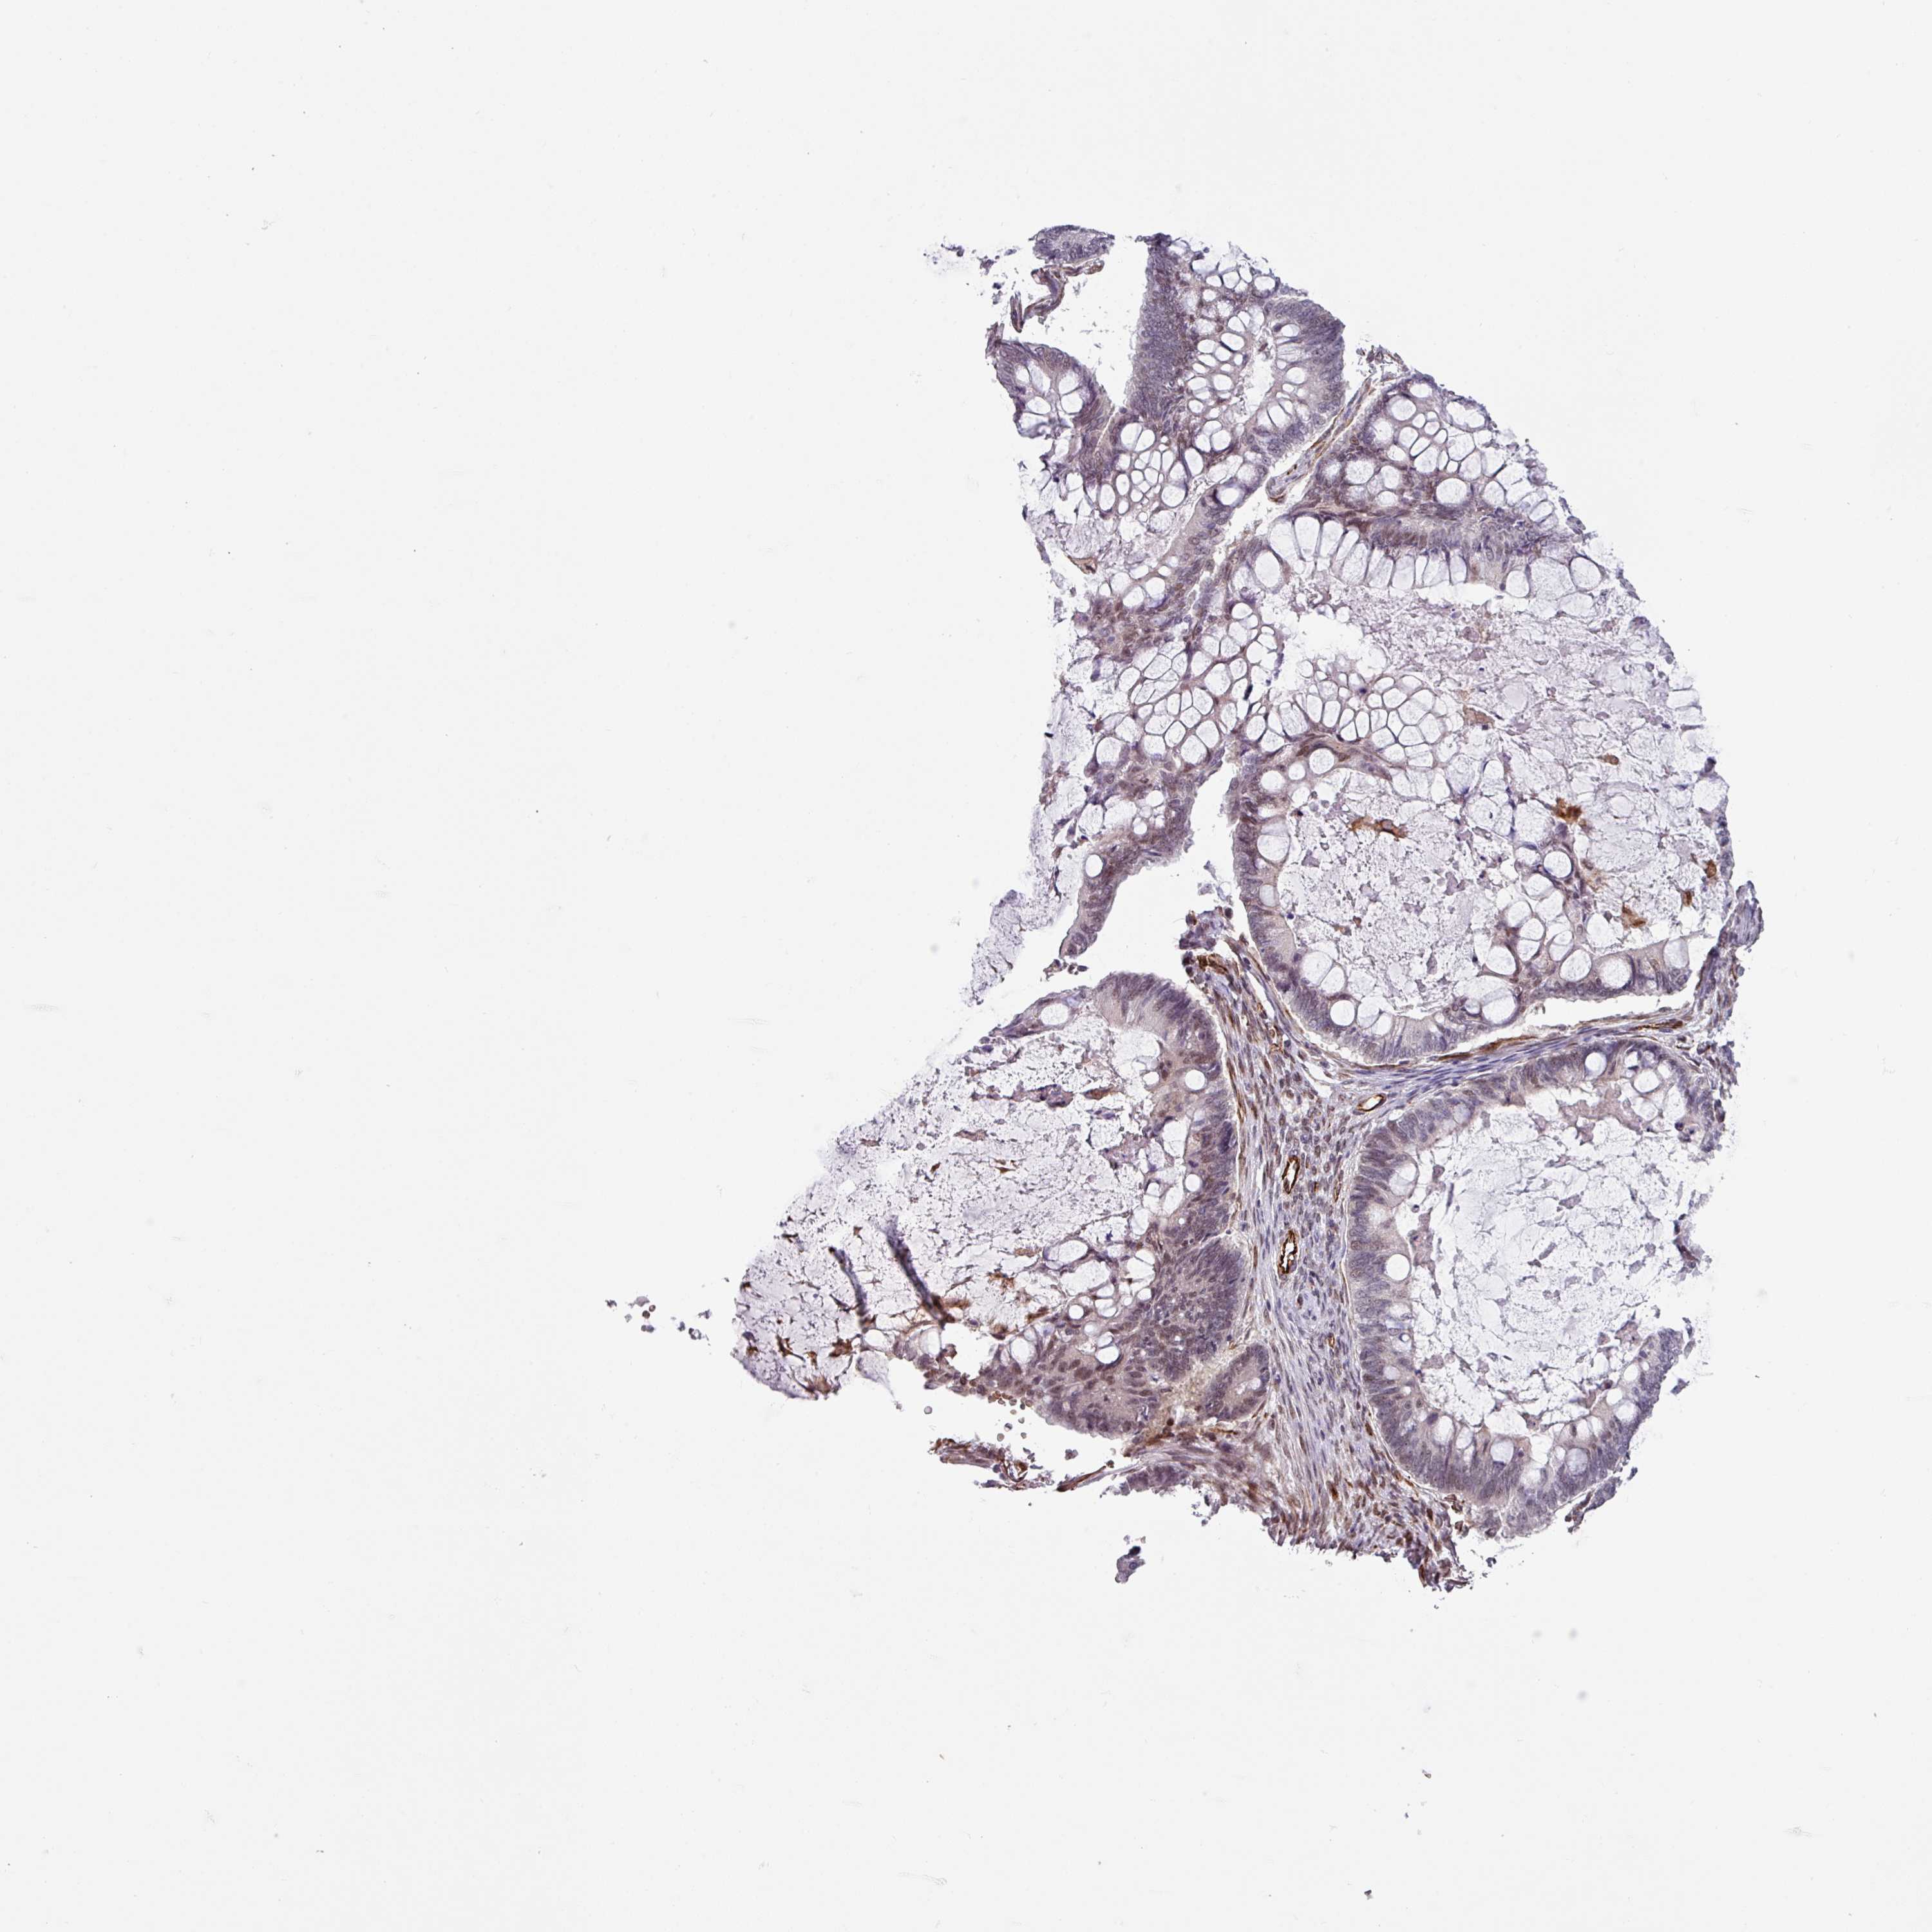

OVARIAN CANCER - Protein expressioni

A mouse-over function shows sample information and annotation data. Click on an image to view it in a full screen mode. Samples can be filtered based on level of antibody staining by selecting one or several of the following categories: high, medium, low and not detected. The assay and annotation is described here.

Note that samples used for immunohistochemistry by the Human Protein Atlas do not correspond to samples in the TCGA dataset.

Antibody stainingi

Antibody staining in the annotated cell types in the current human tissue is reported as not detected, low, medium, or high, based on conventional immunohistochemistry profiling in selected tissues. This score is based on the combination of the staining intensity and fraction of stained cells.

Each image is clickable and will lead to virtual microscopy that enables deeper exploration of all samples and also displays staining intensity scores, fraction scores and subcellular localization as well as patient and tissue information for each sample.

Antibody HPA043368

Staining

High

Medium

Low

Not detected

Intensity

Strong

Moderate

Weak

Negative

Quantity

>75%

75%-25%

<25%

None

Location

Nuclear

Cytoplasmic/membranous

Cytoplasmic/membranous,nuclear

Cystadenocarcinoma, serous, NOS

Carcinoma, endometroid

Cystadenocarcinoma, mucinous, NOS

Carcinoma, NOS